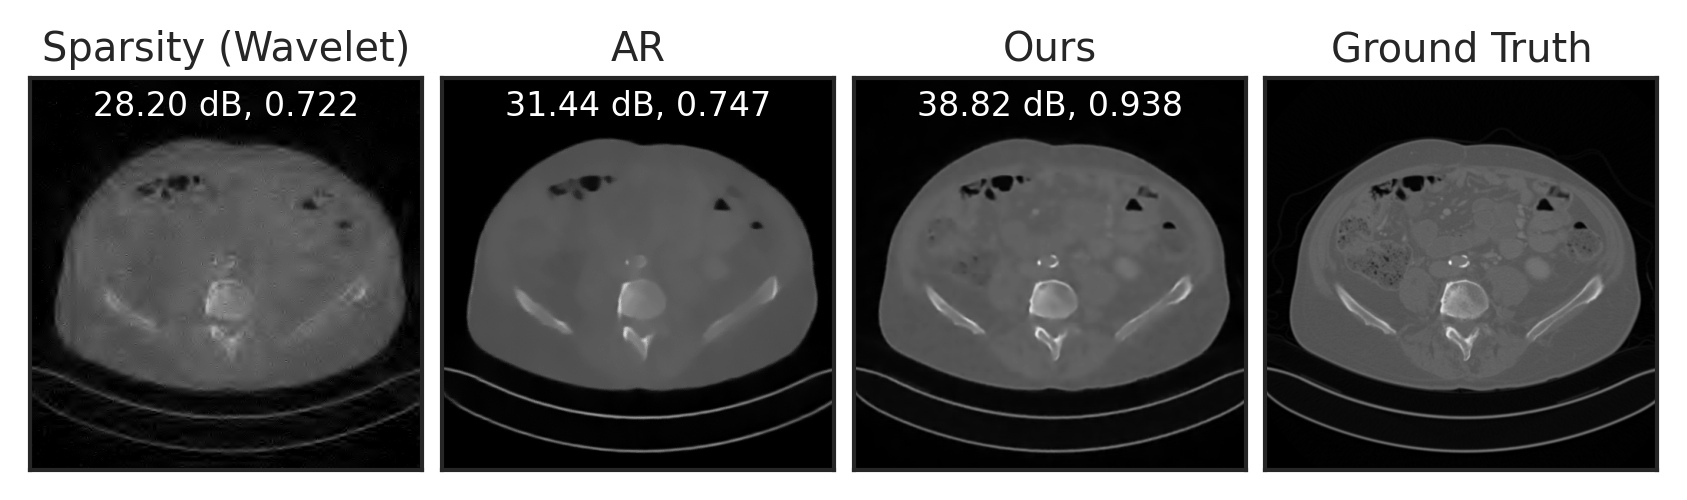

We train LPN on the public Mayo-CT dataset mccollough2016tu of Computed Tomography images, and evaluate it for two inverse tasks: sparse-view CT reconstruction and compressed sensing. For sparse-view CT reconstruction, we compare with the baseline filtered back-projection (FBP) approach willemink2019evolution, the adversarial regularizer (AR) lunz2018adversarial, a learning-based approach with explicit regularizer, and the improved, unrolling-based AR (UAR) mukherjee2021end. UAR is trained to solve the inverse problem for a specific measurement operator (i.e. task-specific), while both AR and LPN are generic regularizers that are applicable to any forward operator (i.e. task-agnostic). In other words, the comparison with UAR is not completely fair (as it is a task-specific method), but we include it here for comparison.

Following Lunz et al. [62], we simulate CT sinograms using a parallel-beam geometry with 200 angles and 400 detectors, with an undersampling rate of . See Section E.4 for experimental details. As visualized in Figure 5(a), compared to the baseline FBP, LPN can significantly reduce noise in the reconstruction. Compared to AR, LPN result is slightly sharper, with higher PNSR. The numerical results in Table 2 show that our method significantly improves over the baseline FBP, outperforms the unsupervised counterpart AR, and performs just slightly worse than the supervised approach UAR – without even having had access to the used forward operator. Figure 5(b) and Table 2 show compressed sensing results with compression rates of and . LPN significantly outperforms the baseline and AR, demonstrating much better generalizability to different forward operators and inverse problems.